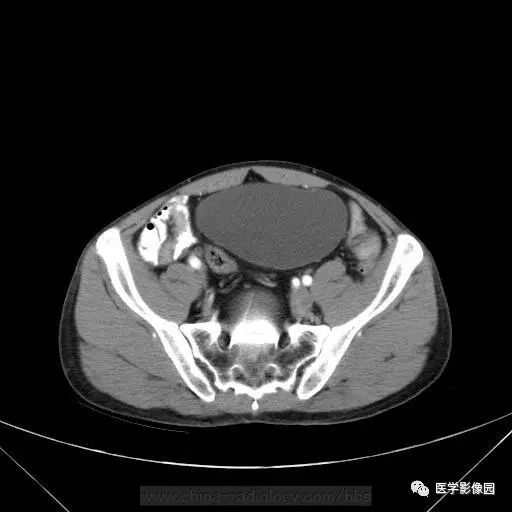

男,46岁,下腹不适一周。

影像学表现:盆腔内直肠后方骶椎骨前方囊性肿块,内见斑点状钙化灶,增强无明显强化。

诊断结果:支气管源性囊肿

一般发生于后腹膜上部多见,发生在骶尾部的少见。CT多表现为膈下圆形或类圆形,界限清晰 低密度囊肿,一般上极较高,可达膈下。因囊液含有蛋白,CT值可较高,达50~60Hu。因其组成成份多不,且可钙化。故有时和畸胎瘤样囊肿难以区别!